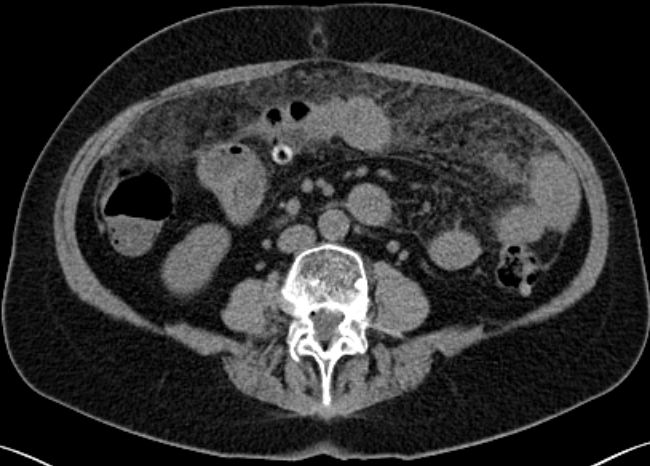

| Peritoneum | 64-jährige Frau mit multiplem Myelom IIIa seit 9 Jahren.

Nach Idarubicin/Dexametason-Induktion hochdosiert Melphalan mit PBSCT.

Dann Bendamustin/Bortezomib. Jetzt extramedulläres peritoneales Rezidiv.![]() | |||